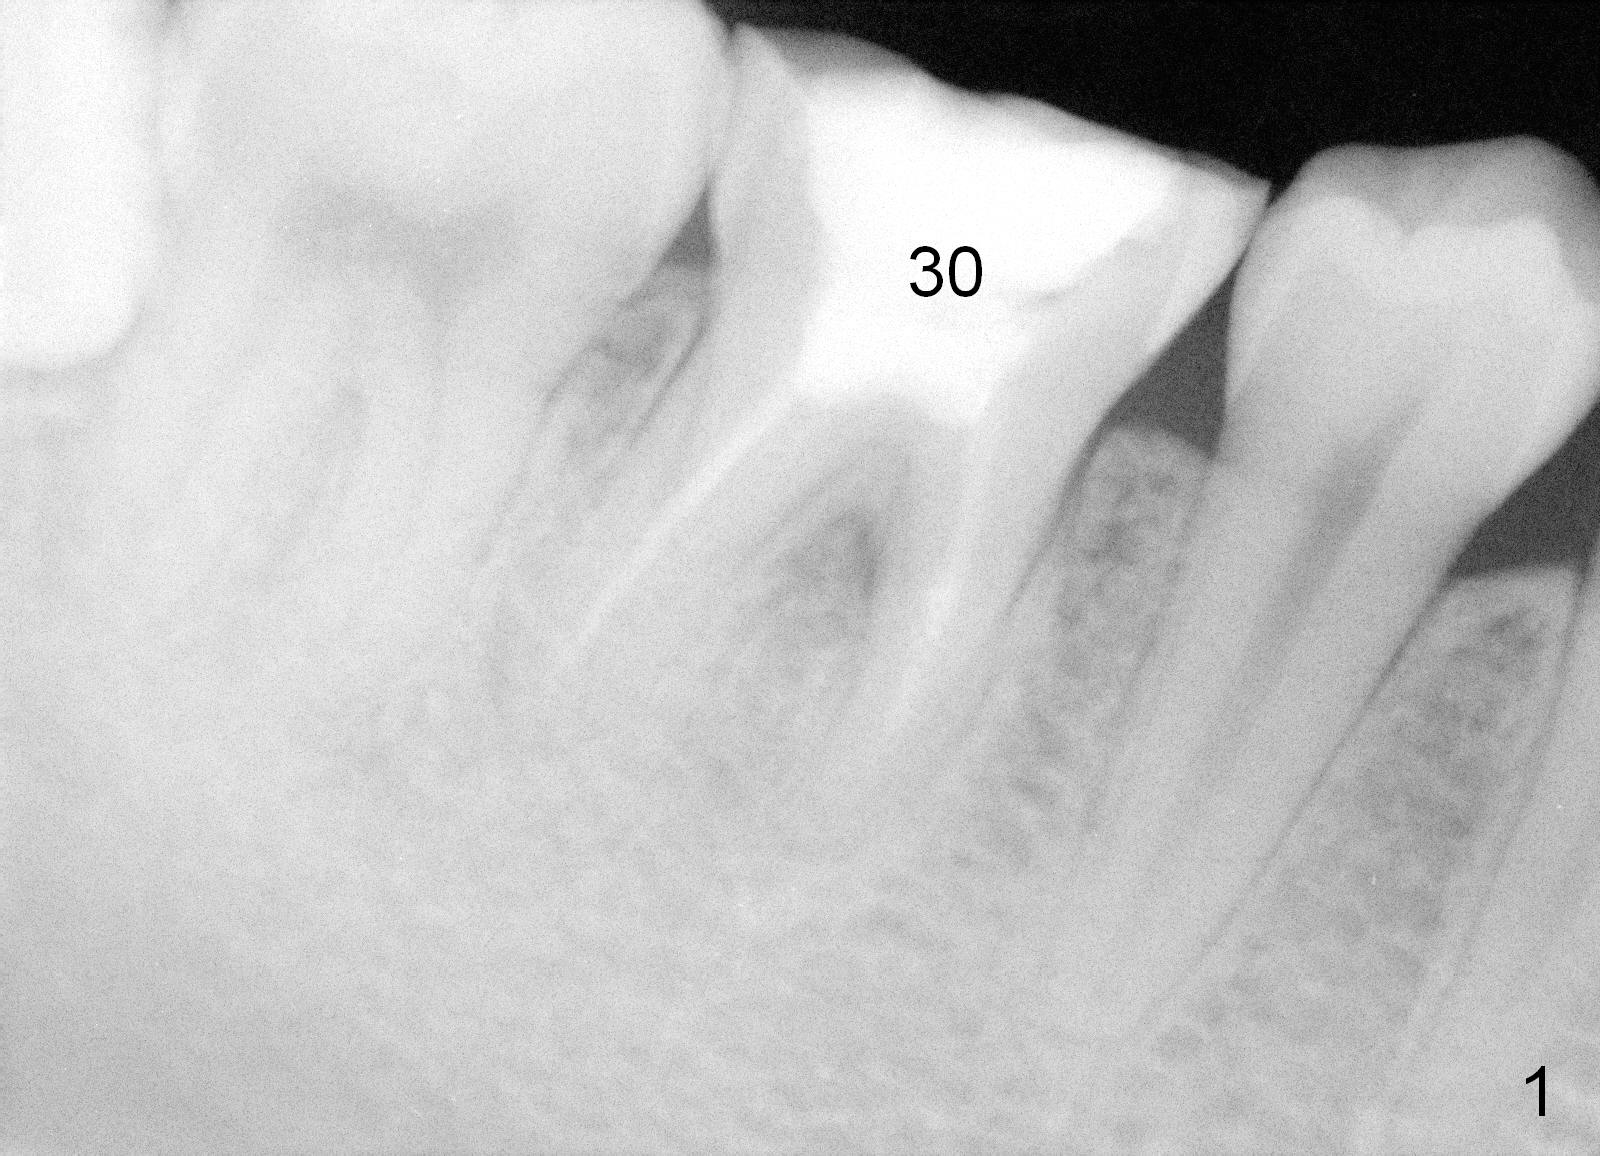

The bone height of the lower right 1st molar of a 24-year-old lady is sufficient (Fig.1).  There is nearly 8 mm between the apices of the 1st lower molar and the Inferior Alveolar Nerve (Fig.2).  Approximately 4-5 mm new bone can be gained for an immediate implant.  Our plan is to use a relatively long and narrow bone-level implant (5.3x14 mm).  Too large implant (6-8 mm) may break off the thin lateral septal wall and slide into the socket.  The drawback using the smaller implant is that more bone graft is going to be used (Fig.2 red circles; collagen plug or membrane (green squares)).

An immediate provisional will be routine fabricated to close the socket opening and keep bone graft and membrane in place.  In addition, the tooth #3 has supraerupted.  The occlusal surface of the tooth #30 has been trimmed substantially (Fig.1).  A temporary abutment may be used.